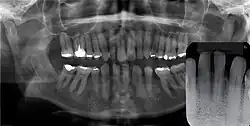

![]() | |

| Epstein's pearl shown in the roof of the mouth on a five-week-old infant | |